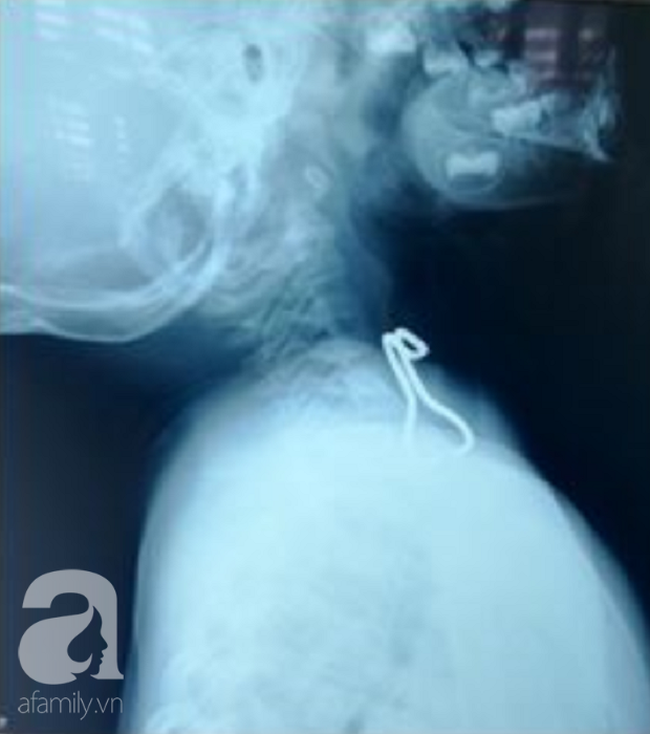

Trường hợp thứ nhất là của một bé gái 6 tuổi (ngụ quận Bình Tân, TP.HCM). Theo lời kể của người nhà trong lúc cầm bút chì chơi, bé gái 6 tuổi vấp té và bị ngòi bút đâm vào mặt, xuyên qua sóng mũi.

Dị vật cắm sâu gần 4 cm vào sát bờ dưới trong ổ mắt, chỉ cần chiếc bút đi chệch vị trí khoảng 1 mm thì bé đã mất mạng ngay lập tức.

Ekip điều trị cho biết, may mắn là đầu bút chì ở dọc tháp mũi đến mặt trước xoang hàm, không chọc thủng nhãn cầu mà xuyên qua vị trí bờ dưới nhãn cầu và hốc mắt. Dị vật nằm rất gần các mạch máu chính dễ gây xuất huyết nếu đường đi chệch hướng.

Dị vật cắm sâu vào mũi bệnh nhân dài 4cm.